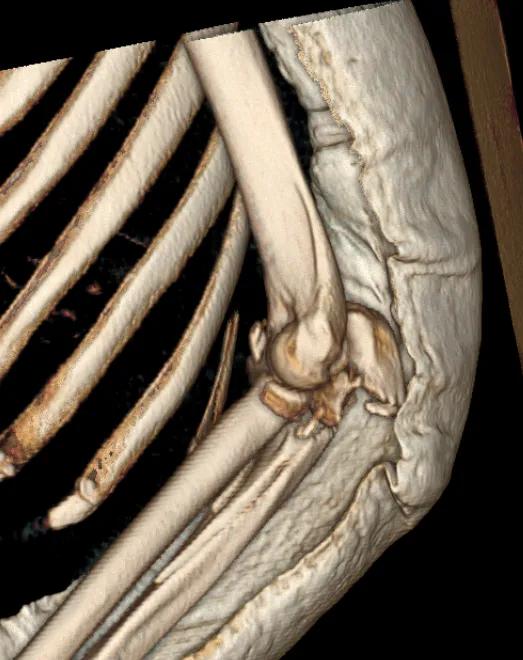

左肘關節CT平掃+三維檢查提示

左肘關節面對位欠佳

左尺骨鷹嘴及橈骨頭骨折

周圍軟組織腫脹